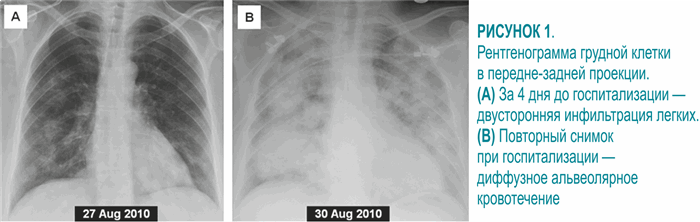

При амбулаторно проведенной рентгенографии грудной клетки за 4 дня до госпитализации выявлена двухсторонняя альвеолярная инфильтрация (рисунок 1А). Повторный снимок в отделении неотложной терапии показал существенное ухудшение, соответствующее диффузному альвеолярному кровотечению (рисунок 1B). Антинуклеарные антитела и ревматоидный фактор были отрицательными, антинейтрофильные цитоплазматические антитела с цитоплазматическим типом свечения (ц-АНЦА) — положительные, их уровень составил 59 ед/мл. АНЦА с перинуклеарным типом свечения (п-АНЦА) и антитела к базальной мембране клубочков отрицательны.